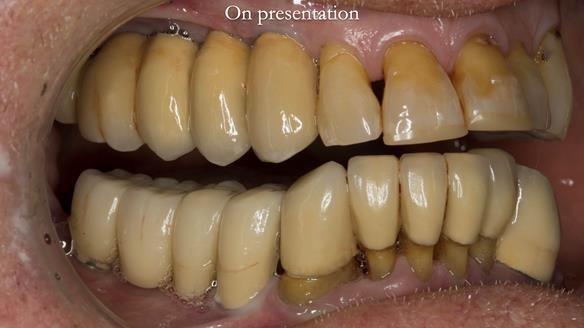

This case was always about function, not aesthetics.

Ken’s teeth were never going to look perfect.

There were stained composites, old restorations, and obvious wear.

That was accepted from the outset.

The way Rowan lengthened the teeth — particularly in the upper RPD — to match the existing gingival recession on the remaining teeth was superb. The dentures sit naturally within the context of the rest of the mouth.